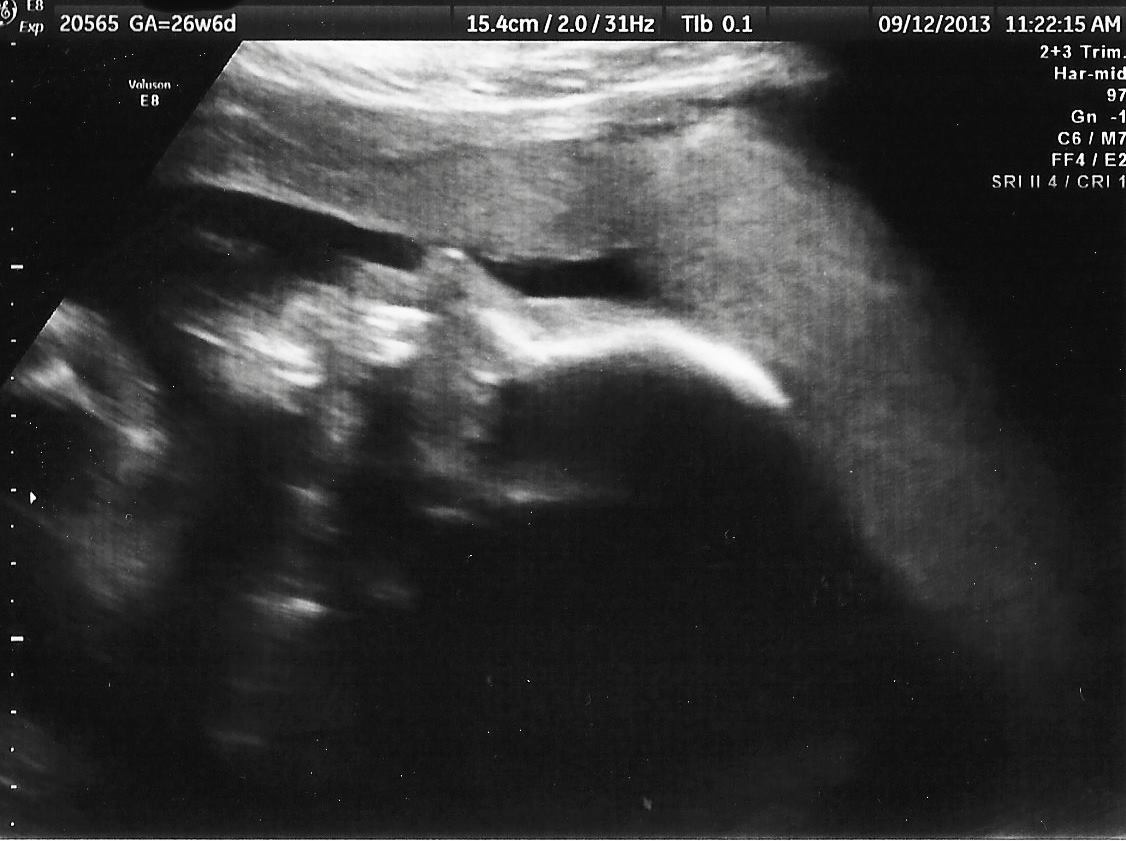

I went to another forum people keep saying maybe a boy I am very stress I need more opinions please !!! I was told a girl but now I can't be sure :(

Looks NOTHING like my boys. That's a girl!! Congrats!

I'm no expert but even to me that ohoto screams girl! X

Looks like a girl to me! Congrats x

It's a tricky angle but sure looks girly to me. Congrats!

That looks exactly what my girls scans look like, don't stress, its a Girl!

Thats identical to my daughters' scans